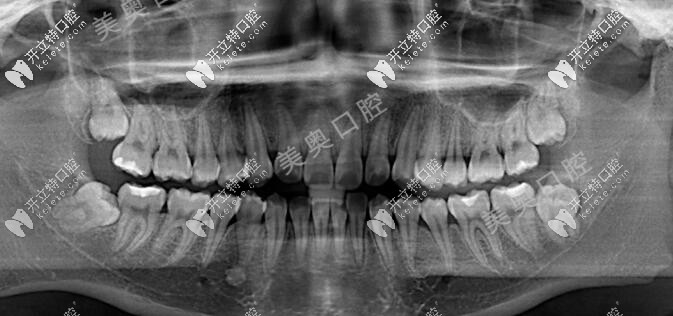

從口內(nèi)照片可以看出來(lái),牙列存在擁擠情況,且中線(xiàn)不齊,X線(xiàn)片顯示顧客的四顆智齒也是正在萌出,位置相對(duì)比較正常,牙弓有輕微的2mm擁擠,矯正前的左右面容也不對(duì)稱(chēng)。